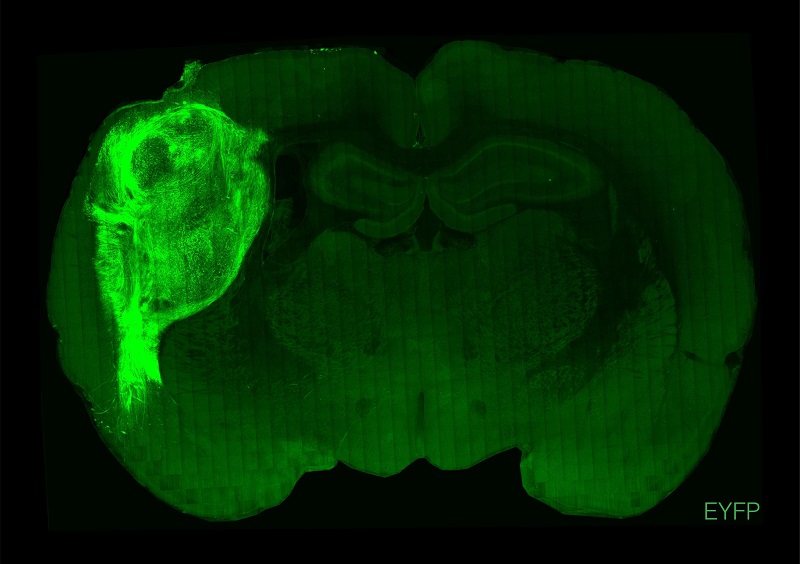

用荧光蛋白标记的人类类脑在大鼠的大脑中。

图片来源:斯坦福大学